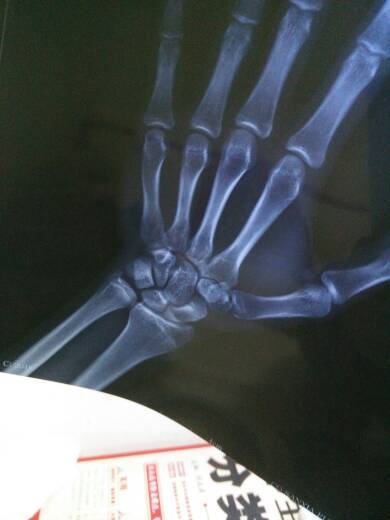

求好心人帮我看看骨骼闭合没?还能不能长 我刚好16 求好心人帮我看看骨骼闭合没?还能不能长。我刚好16 点击展开 胆小鬼_plJl 2015-01-13 22:01 为您推荐: 其他回答 您好;建议做一个骨骺线方面的检查,如果骨骺线将要闭合并没有完全闭合的情况可以短期使用生长激素.应多吃蔬菜和高蛋白食物和优质蛋白食物和含钙丰富的食物和含锌丰富的食物.防止偏食.保证休息时间和质量.多参加体育锻炼.如跳绳.篮球等. gaoguo120 2015-01-14 10:04 相关问题 16-19岁没怎么长个子别人都飞了而我还是那16岁小孩子一点都没变身体骨骼瘦小该怎么办 16-19岁没怎么长个子别人都飞了而我还是那16岁小孩子一点都没变身体骨骼瘦小该怎么办 哪位好心人帮我看看我这样的腿算不算粗,是不是有点婴儿肥